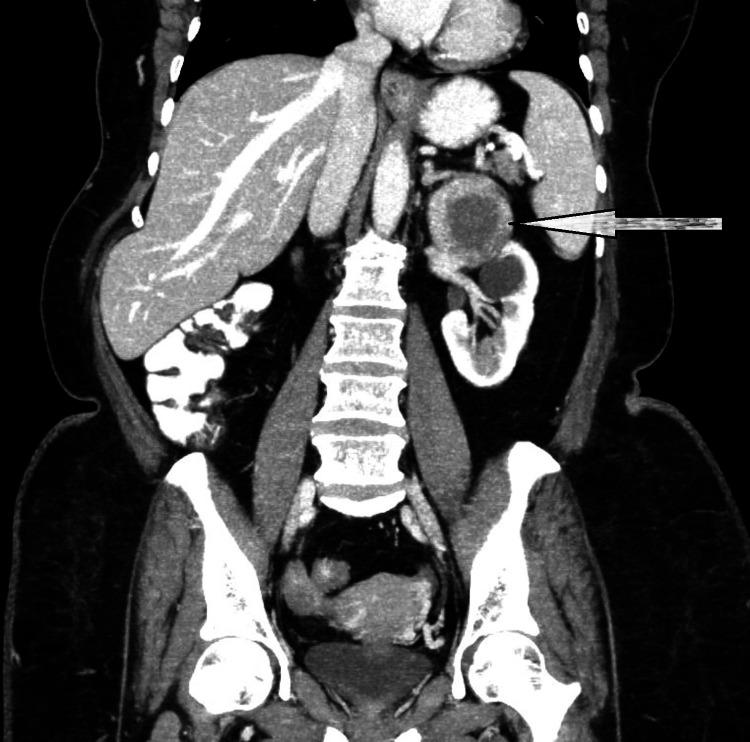

Pheochromocytomas are rare adrenal medulla tumors originating from chromaffin cells, accounting for 10% of primary adrenal neoplasms. Oncocytic variants of pheochromocytomas are rare and have been reported in only 150 cases. This report describes the case of a 60-year-old female who arrived with a non-functional adrenal tumor. This case report emphasizes the importance of a comprehensive histological and immunohistochemical study for diagnosing this rare diagnostic entity and its potential diagnostic pitfalls.

嗜铬细胞瘤是起源于嗜铬细胞的罕见肾上腺髓质肿瘤,占原发性肾上腺肿瘤的10%。嗜铬细胞瘤的嗜酸细胞变体罕见,仅报道过150例。本报告描述了一名60岁女性因无功能肾上腺肿瘤前来就诊的病例。本病例报告强调了全面的组织学和免疫组化研究对于诊断这种罕见诊断实体及其潜在诊断陷阱的重要性。